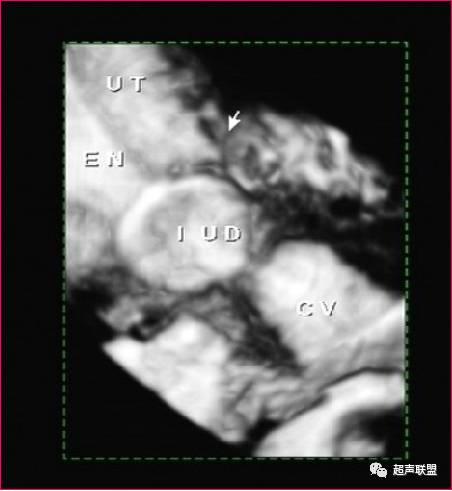

节育器外游

节育环(IUD)位于宫颈(CX)左侧的盆腔内.

(经阴道超声)

超声表现为子宫腔内无节育器显示,节育器可穿透宫壁落入腹腔,包裹于肠管中,从而形成纤维粘连或机化,在腹腔内、阔韧带、附件区或直肠窝区有强回声节育器图像。节育器外游至盆腔,因肠道气体干扰不易寻找,应多角度仔细观察,节育器外游至肠间与肠道气体相混不易分辨,超声仪无能为力,须借助X线检查。偶尔IUD可穿入膀胱,此时可见带有彗星尾征的强回声带穿过膀胱壁而进人膀胱腔。鉴别诊断:节育器外游至膀胱须与膀胱结石相鉴别,结石随患者体位不同而改变,位置变化较大,节育器多因炎性粘连而固定不动。